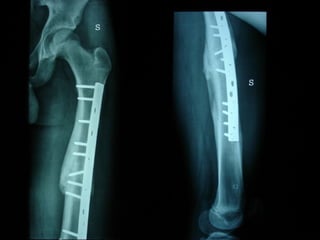

Dal Gennaio 2000 al Febbraio 2006 abbiamo trattato 167 fratture chiuse  con placca percutanea  in 164 pazienti :  27 lesioni diafisarie di gamba, 12 piloni tibiali ,  11 fratture prossimali di tibia, 36 fratture sovracondiloidee di femore, 17 fratture diafisarie di femore, 43 fratture metaepifisarie prossimali di omero, 21 diafisarie d’omero.  156 guarigioni 8 fallimenti

I buoni risultati ottenuti dipendono da 5 punti fondamentali:   una accurata riduzione percutanea della frattura  precise vie di accesso  l’utilizzo della placca che consenta il più lungo braccio di leva possibile il pretensionamento della placca  una sintesi con un ridotto numero di viti

Dal Gennaio 2000 al Dicembre 2005 27 placche LISS di femore

INDICAZIONI COMUNI Fratture sovracondiloidee Fratture intercondiliodee Fratture diafisarie distali PARTICOLARI Fratture con grave osteoporosi Fratture periprotesiche

VANTAGGI CHIRURGIA MININVASIVA Mini Open Inserimento della placca sottocutaneo per scivolamento Viti percutanee Preservazione dei tessuti molli Ridotto danno vascolare Rapida ripresa funzionale

F, 68 y

LISS  NCB

NCB